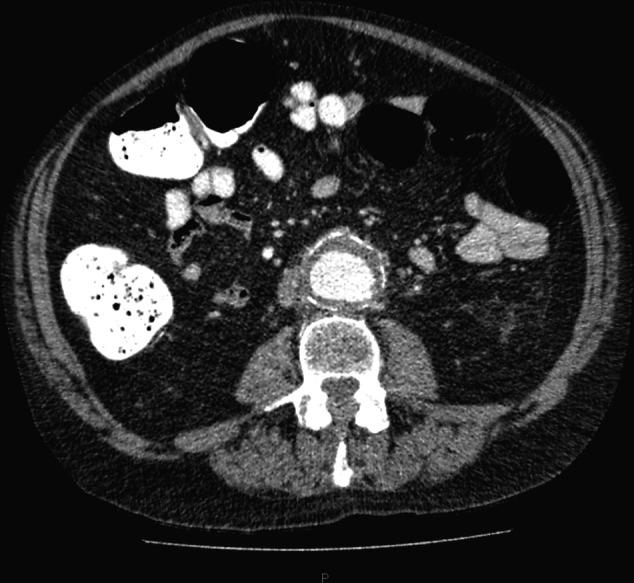

尿潴留的解除会引发腹主动脉瘤破裂吗?

Can release of urinary retention trigger abdominal aortic aneurysm rupture?

Only 50% of abdominal aortic aneurysms present with the classic triad of hypotension, back pain and a pulsatile abdominal mass. This variability in symptoms can delay diagnosis and treatment. We present the case of a patient presenting with a unique combination of symptoms suggesting that decompression of urinary retention can lead to abdominal aortic aneurysm rupture.

只有50%的腹主动脉瘤患者会出现低血压、背痛和搏动性腹部肿块这一典型三联征。症状的这种变异性会延误诊断和治疗。我们报告一例患者,其症状的独特组合提示尿潴留减压可导致腹主动脉瘤破裂。